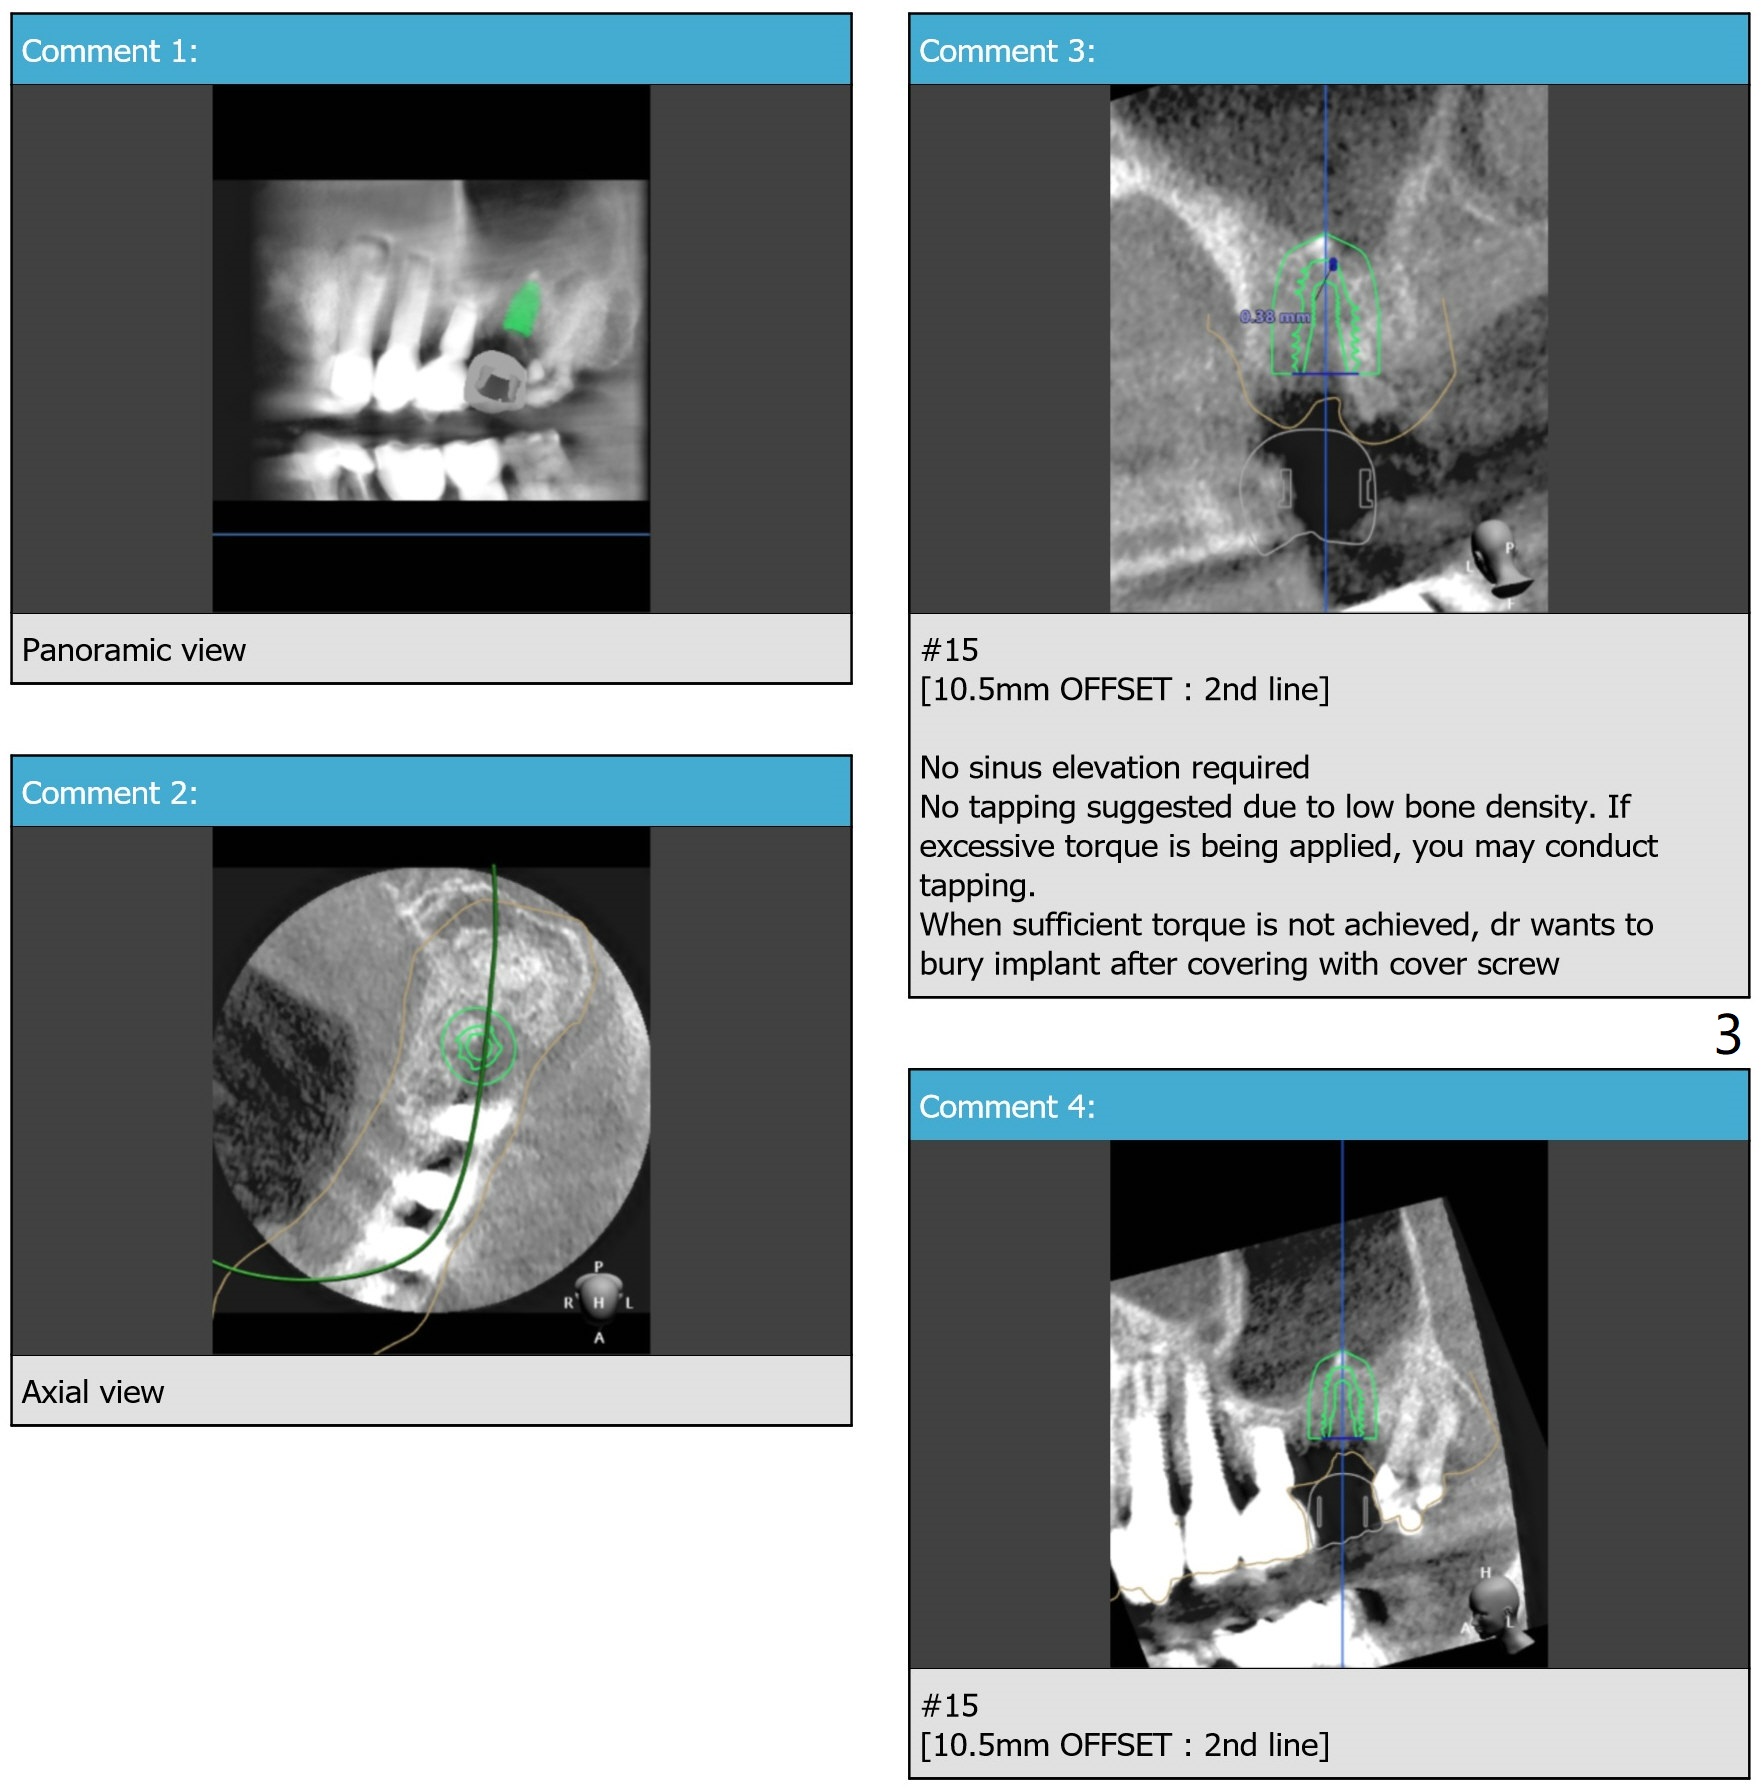

Low Bone Density after Bone Graft

A 89-year-old man. After the last 2nd drill, use 2.2 mm drill to the depth to see whether sinus membrane is perforated or not. Then increase drill diameter.